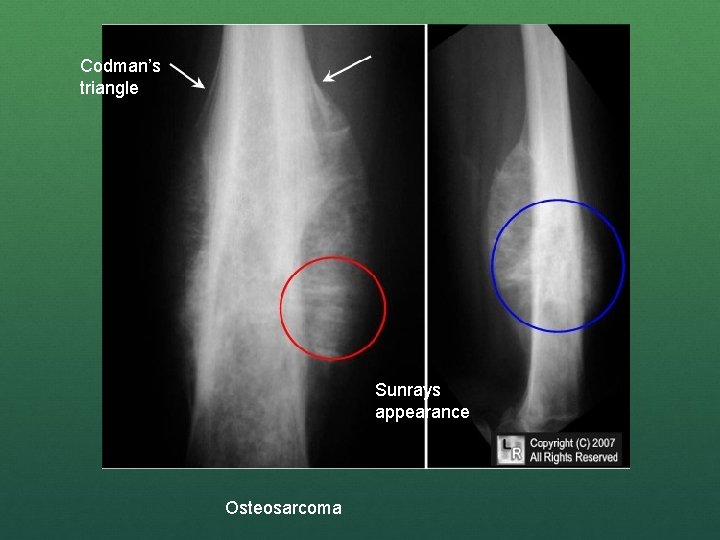

n Classic X-ray findings: 1. 2. 3. 4. Codman's triangle (periosteal elevation) Sunburst pattern/Sunrays appearance Bone destruction Ill-defined margins

Codman’s triangle Sunrays appearance Osteosarcoma